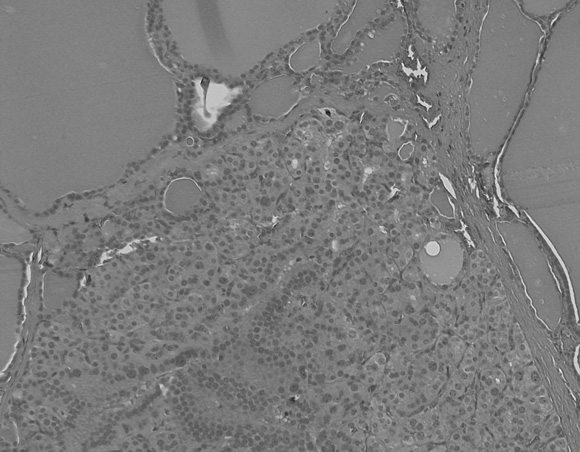

4: Irradiated thyroid gland

An irradiated thyroid gland containing a hypercellular nodule consisting almost entirely of microfollicles and showing focal nuclear atypia.

It is possible that radiation-induced thyroid neoplasia in childhood survivors of cancer is different from neoplasia arising spontaneously. Post-irradiation cancers arise in glands with widespread histological abnormality (Box 4), as in our study and as seen in children who were exposed to radiation in the Chernobyl disaster.17 Thyroid carcinoma in children and adolescents under standard conditions has an incidence of 0.5 per million per year.18 It is also unknown whether microcarcinomas in the young thyroid previously exposed to irradiation (present in a third of our patients) have different prognosis to those in older glands, where the long term prognosis is generally favourable.19